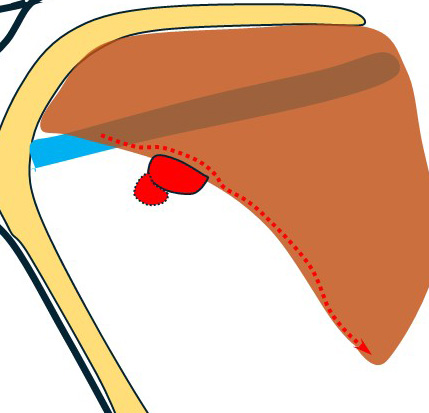

大きなリンパ節(左図 黄色)をこの視野で腋窩静脈から外していったが一部は(小胸筋裏を超えて)その奥のリンパ節に連続しており、この視野から(この大きなリンパ節を)外すことは断念して(レベルⅢ郭清の際に)外す方針とした。

この部分の拡大図

小胸筋内側(奥)は膜で連続しておりその奥は見えない。

鎖骨下静脈はこの膜で視認できないため、これの損傷を防ぐために、小胸筋裏に指を入れこの静脈の走行を確認しつつ、それより尾側で小胸筋膜を小胸筋に沿って切離し貫通した。

この膜が切離された部分にテープを入れて、小胸筋を手前(外側)に思いっきりけん引した。

これにより先に途中まで外していた大きなレベルⅡリンパ節(図の黄色)とそれに連続していたレベルⅢ(図の赤色)が鎖骨下静脈とともに直視下となり、慎重に小血管を処理しながら鎖骨下静脈から外して郭清。

このまま鎖骨下静脈及び胸壁からバイクランプでレベルⅢ群を全て郭清した。